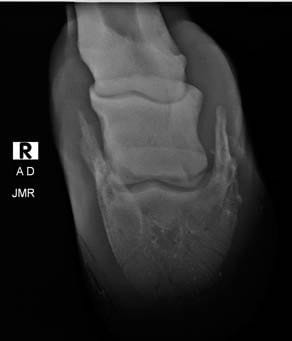

La radiología digital directa es una herramienta indispensable para el estudio v valoración en numerosas áreas de la atención veterinaria: valoración de cojeras, exámenes pre-compra, estudios radiológicos, diagnósticos más precisos en patologías, heridas, enfermedad…

Por eso nos mantenemos al día y nos renovamos con nuevos equipos de radiología digital directa que incorporan herramientas de diagnóstico y valoración con ventajas como:

- Radiografía en pantalla en 4 segundos

- Herramientas de medidas más completas y potentes

- Medidas e imagen 3D para evaluación del pie equino